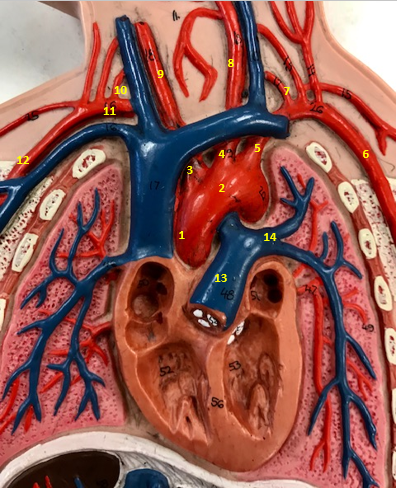

Aorta

Name #2

Brings blood out of left ventricle

Function of aorta

Brachiocephalic artery

Name #3

Supplies oxygenated blood to right arm shoulder neck and head

Function of brachiocephalic artery

Left common carotid artery

Name #4

Supplies oxygenated blood to left neck and head

Function of left common carotid artery

Left subclavian artery

Name #5

Supplies oxygenated blood to left arm shoulder

Function of left subclavian artery

Left axillery artery

Name #6

supplies blood to left armpit and upper limb

Function left axillary artery (6)

Left vertebral artery

Name #7

Supplies blood to brain and spinal cord

Function of left vertebral artery (7)

Left common carotid artery

Name #8

Supplies blood to left neck and head

Function of left common carotid artery (8)

Right common carotid artery

Name #9

Supplies oxygenated blood to right neck and head

Function of right common carotid artery (9)

Right vertebral artery

Name #10

Supplies blood to brain and spinal cord

Function of right vertebral artery (10)

Right subclavian artery

Name #11

Supplies blood to right arm and shoulder

Function of right subclavian artery

Right axillery artery

Name #12

Supplies blood to right armpit and upper limb

Function of right axillery artery (12)

Pulmonary trunk

Name #13

Bring blood out of right ventricle to lungs

Function of pulmonary trunk (13)

Left pulmonary artery

Name #14

Bring blood to left lung

Function of left pulmonary artery (14)